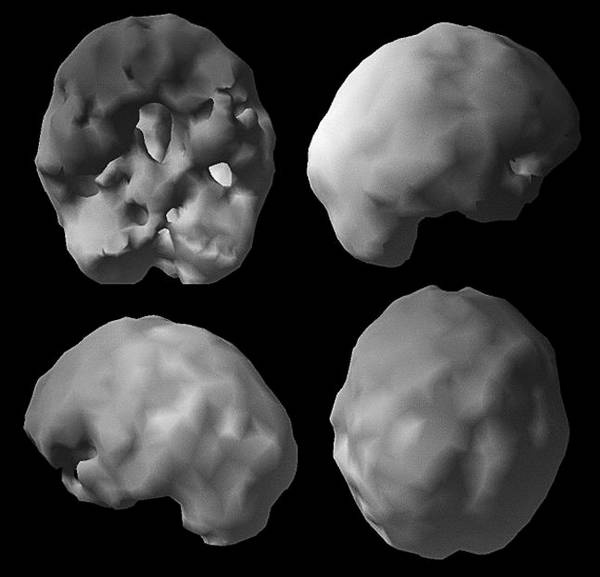

Больше узнать о состоянии здоровья своего мозга и риске развития болезни Альцгеймера поможет томограмма ОЭКТ. Когда мне исполнилось 50, мой лечащий врач назначил плановую колоноскопию. «А почему вы не хотите проверить мой мозг, – поинтересовался я, – разве другой конец туловища не столь важен?» Как узнать, что происходит в мозге, если не обследовать его? Я верю, что томограф в ближайшем будущем станет таким же привычным инструментом диагностики, как маммограф или колоноскоп. Он принесет особую пользу людям из группы риска и тем, у кого уже появились «ранние» симптомы. Поскольку большинство врачей еще не привыкли к томографии, многие пациенты узнают о своих проблемах «в голове», когда уже слишком поздно. А ведь на раннем этапе эти заболевания можно корректировать. Вот пример. Эд Эду семьдесят два, его дочь Кэндис привезла его к нам на прием из Ванкувера, Британская Колумбия. Кэндис была встревожена забывчивостью отца. Его настроение было хуже обычного, а суждения не столь хороши, как прежде. Некоторые финансовые счета он оплачивал дважды, а о других мог забыть. Когда она отвела его к местному невропатологу, тот диагностировал болезнь Альцгеймера, не сделав томограмму его мозга. Кэндис прочитала мою книгу «Измените свой мозг – и жизнь изменится» и расстроилась, что врач не сделал томограмму. Скан мозга Эда (горизонтальные срезы мозга показаны по направлению сверху вниз) ![]() См. срезы 15 и 16 и увидите «лобстера» Скан нормального мозга ![]() Полная, равномерная, симметричная активность Скан ОЭКТ мозга Эда ![]() Нетипичная структура для болезни Альцгеймера, мы видим увеличенные желудочки («дыра» в середине) и маленький мозжечок (в основании) Врач ответил, что уверен в своем диагнозе и не нуждается в подтверждении. Меня такое отношение всегда неприятно удивляет. Недовольная поведением врача, Кэндис привезла Эда к нам. На скане мозга Эда было видно, что желудочки мозга (заполненные жидкостью полости) увеличены. Такой рисунок на томограмме я называю лобстером, потому что он похож на перевернутого омара. Еще у Эда был слишком маленький мозжечок. Томограмма Эда определенно не походила на типичную картину поражения, которую мы наблюдаем при болезни Альцгеймера (низкая активность височных и теменных долей). Зато картина, как у Эда, часто обнаруживается при заболевании под названием «гидроцефалия с нормальным давлением». При ней блокируется нормальный отток жидкости из желудочков мозга и количество жидкости в них постепенно возрастает. Одновременно могут проявляться такие симптомы, как недержание мочи и нарушение походки, хотя и не обязательно. Поскольку этих симптомов у Эда не было, его невролог даже не подумал о другом диагнозе. А состояние Эда продолжало ухудшаться. Увидев скан, я сразу назначил консультацию с нейрохирургом. Тот согласился с моим диагнозом и провел шунтирование мозга Эда. Память восстановилась в течение 3 недель. Как можно помочь, если не посмотреть на пострадавший орган? ШАГ 3. Сосредоточьтесь на уменьшении специфических факторов риска Итак, вы представляете, какие факторы риска существуют. Что с ними делать? Вот список факторов и действий. • Фактор риска: Член семьи с болезнью Альцгеймера или схожим нарушением, либо у вас есть ген APO e4. • Действие: Проведите ранний скрининг и со всей серьезностью как можно раньше займитесь профилактикой. Реализуйте все описанные в этой книге стратегии прямо сейчас. • Фактор риска: Единичная черепно-мозговая травма или несколько черепно-мозговых травм. • Действие: Предотвращайте повторные черепно-мозговые травмы, как можно скорее реализуйте стратегии профилактики. • Фактор риска: Алкоголизм, наркотическая зависимость или курение в прошлом либо настоящем. • Действие: Остановите лечение и ищите скрытые причины, как можно раньше начинайте стратегии профилактики. • Фактор риска: Тяжелая депрессия или СДВ(Г), диагностированные врачом в прошлом или настоящем. • Действие: Лечитесь, занимайтесь профилактикой. • Фактор риска: Инсульт, болезнь сердца, высокий уровень холестерина, артериальная гипертензия, диабет, история лечения рака, эпилептические припадки в прошлом или настоящем. • Действие: Лечение и стратегии профилактики. • Фактор риска: Ограниченная физическая нагрузка (меньше двух получасовых тренировок в неделю). • Действие: тренируйтесь три раза в неделю или больше. • Фактор риска: Образование ниже среднего школьного или работа, не требующая периодического освоения новой информации. • Действие: Учитесь всю жизнь, непрерывно. • Фактор риска: Сонное апноэ. • Действие: Пройдите осмотр и займитесь лечением апноэ. • Фактор риска: Дефицит эстрогена или тестостерона. • Действие: Подумайте о гормонозаместительной терапии. Думаю, вы поняли принцип. Устраните факторы риска, которые поддаются уменьшению, и работайте над долгосрочным здоровьем мозга. ШАГ 4. Поддерживайте активность тела и мозга В следующих главах вы увидите, что физические и умственные тренировки – это лучший способ сохранить молодость мозга. Тренировка ума помогает мозгу укрепить имеющиеся синаптические связи и создавать новые. Больше об интеллектуальных тренировках вы узнаете в главе 5. Физические упражнения повышают приток крови к мозгу, улучшают его обеспечение кислородом и помогают защитить мозг от вредных молекул, таких как свободные радикалы. Подробнее о физических упражнениях будет рассказано в главе 3. ШАГ 5. Принимайте пищевые добавки для поддержания здоровой функции мозга О пищевых добавках накоплено много информации, а также дезинформации. Отделить истину от заблуждений очень важно, потому что некоторые добавки действительно работают. Каждый день принимайте поливитамины и рыбий жир. Проверьте свои показатели витамина D и при необходимости оптимизируйте их. Вот еще несколько доказавших свою эффективность добавок. • Рыбий жир и куркумин для уменьшения воспалений. • N-ацетилцистеин и альфа-липоевая кислота – чтобы повысить сопротивляемость тела свободным радикалам и окислительному стрессу. |